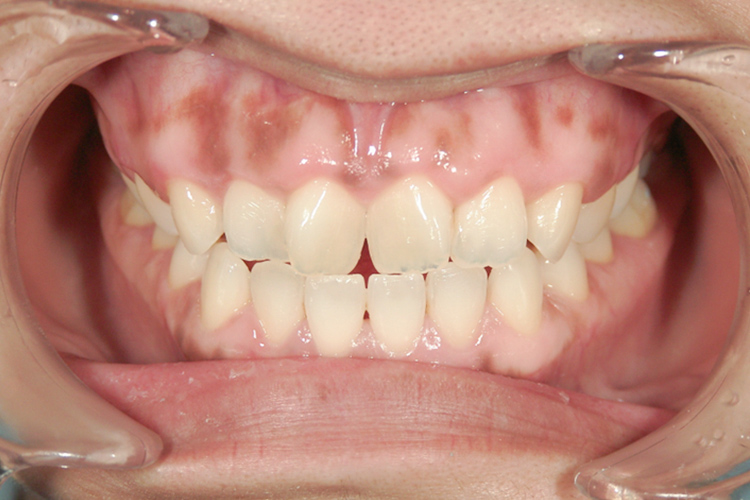

治療前

治療後